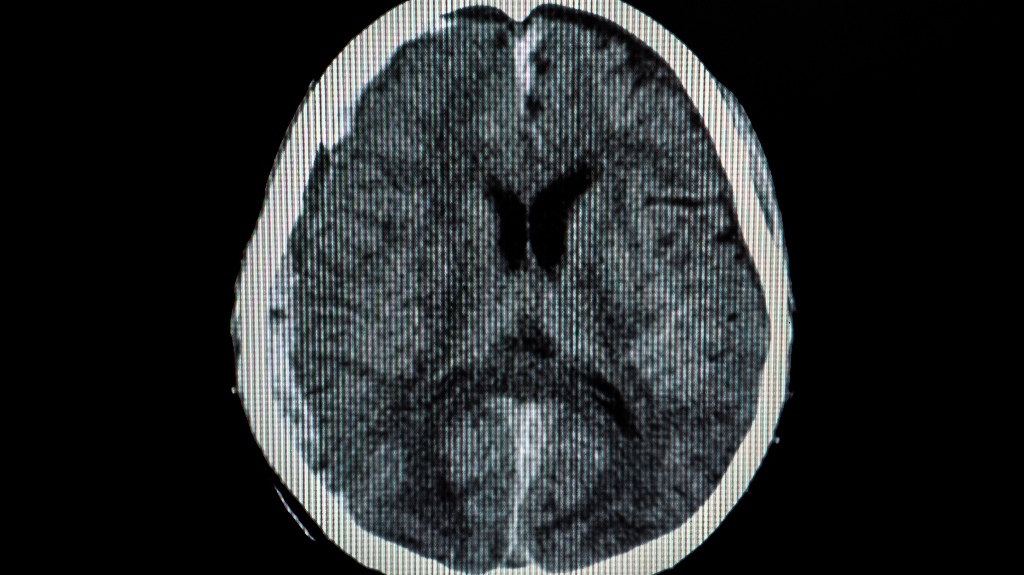

- Radiologists: Radiologists tell the jury about your CT scans, MRIs, and other imaging in interpreting your brain injuries.

The doctor will talk about how serious your injuries are. They will utilize scans and other evidence to prove how badly you were hurt.